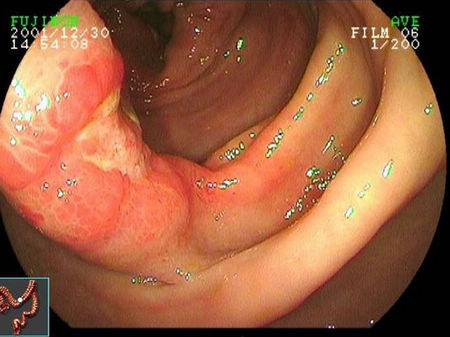

克罗恩病

克罗恩病是一种消化道的慢性、反复发作和非特异性的透壁性炎症, 病变呈节段性分布, 可累及消化道任何部位,其中以末端回肠最为常见,结肠和肛门病变也较多。

克罗恩病可累及全消化道,根据所累及的范围,可分为小肠型(30% ~ 40%)、小肠及结肠型(40% ~ 55%)、结肠型(15% ~ 25%)。累及小肠者,回盲部受侵犯的达90%以上。

按照临床表现的特点,又可分为梗阻型和成瘘型。内镜下可见跳跃性病变、裂隙样溃疡、狭窄等。内镜下粘膜活检往往不能得到充分的病理诊断依据,但有时可发现肉芽肿等病变。

结肠克罗恩病

克罗恩病中,局限于结肠的约占1/4。一般地,结肠克罗恩病不累及直肠,病变之间粘膜正常(跳跃性病变)、溃疡呈裂隙样、粘膜可呈铺路石样。

10 ~ 15%的病例在诊断为克罗恩病后的一年内被重新诊断为溃疡性结肠炎。对于不能确定诊断的局限于结肠的炎性肠病可考虑未定型结肠炎(indeterminate colitis)的诊断,但该诊断不宜滥用。